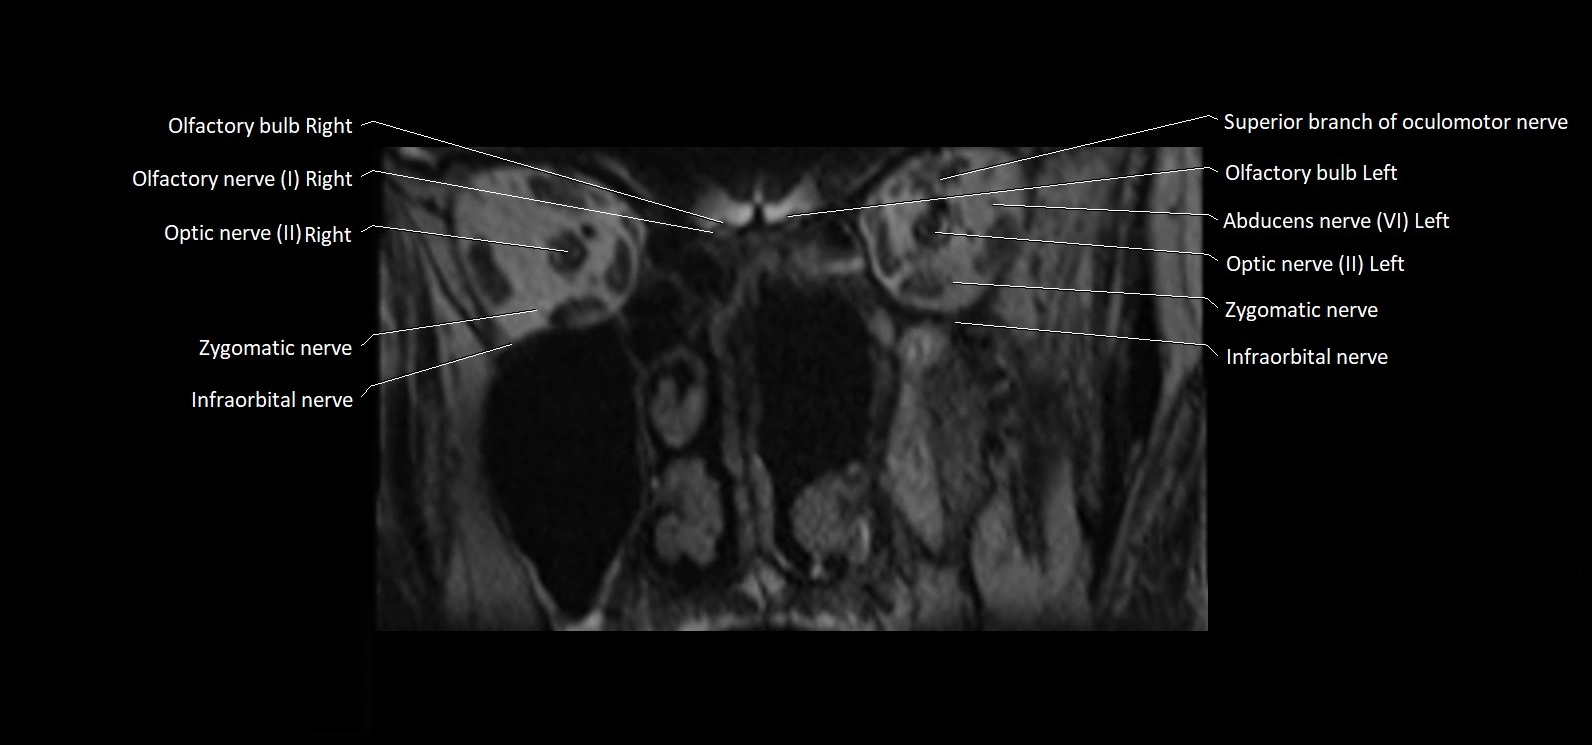

MRI Appearance

• The abducens nerve is a small, thin, linear structure

• Best visualized on high-resolution T2-weighted 3D MRI sequences (e.g., FIESTA or CISS)

• Seen as a hypointense (dark) line running from the brainstem at the pontomedullary junction, traversing the prepontine cistern, and entering Dorello’s canal under the petrosphenoidal ligament, then into the cavernous sinus, and finally the orbit

• May be challenging to visualize in standard MRI due to its small size

• Pathology may be inferred by absence, displacement, or enhancement of the nerve